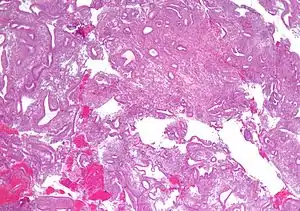

| Micrograph showing simple endometrial hyperplasia, where the gland-to-stroma ratio is preserved but the glands have an irregular shape and/or are dilated. Endometrial biopsy. H&E stain. | |

- Endometrial hyperplasia (simple or complex) - Irregularity and cystic expansion of glands (simple) or crowding and budding of glands (complex) without worrisome changes in the appearance of individual gland cells. In one study, 1.6% of patients diagnosed with these abnormalities eventually developed endometrial cancer.[6]